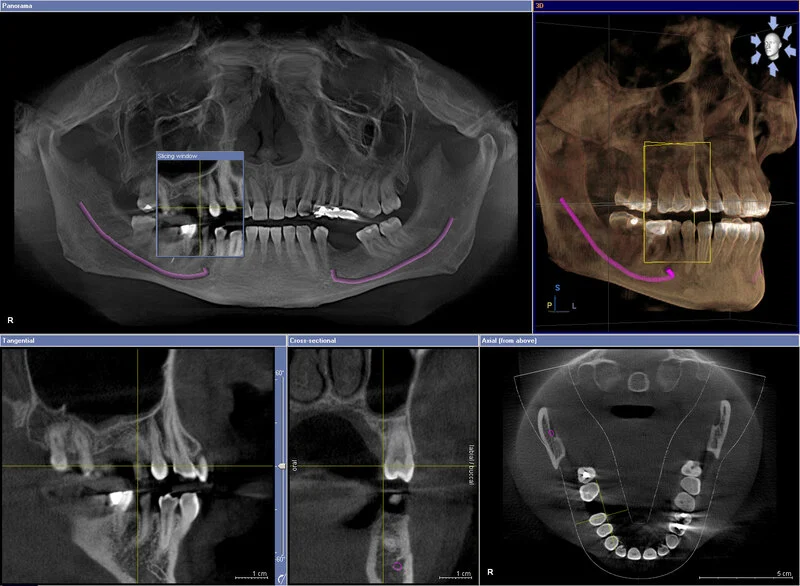

Phim CT Cone Beam 3D (CBCT)

Đây là công nghệ tiên tiến nhất. Nó cung cấp hình ảnh 3 chiều (3D) của cấu trúc xương, răng, dây thần kinh và mô mềm. Đây là “tiêu chuẩn vàng” bắt buộc khi cấy ghép Implant, nhổ răng khôn mọc ngầm phức tạp hoặc điều trị tủy lại.